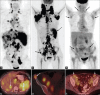

Generalized lymphadenopathy is a common and often vexing clinical problem caused by various inflammatory, infective and malignant diseases. We aimed to review briefly and highlight the potential role of (18)F-2-fluoro-2-deoxy-glucose ((18)F-FDG) positron emission tomography/computed tomography (PET/CT) in such patients. (18)F-FDG PET/CT can play an important role in the management of generalized lymphadenopathy. It can help in making an etiological diagnosis; can detect extranodal sites of involvement and employed for monitoring response to therapy.